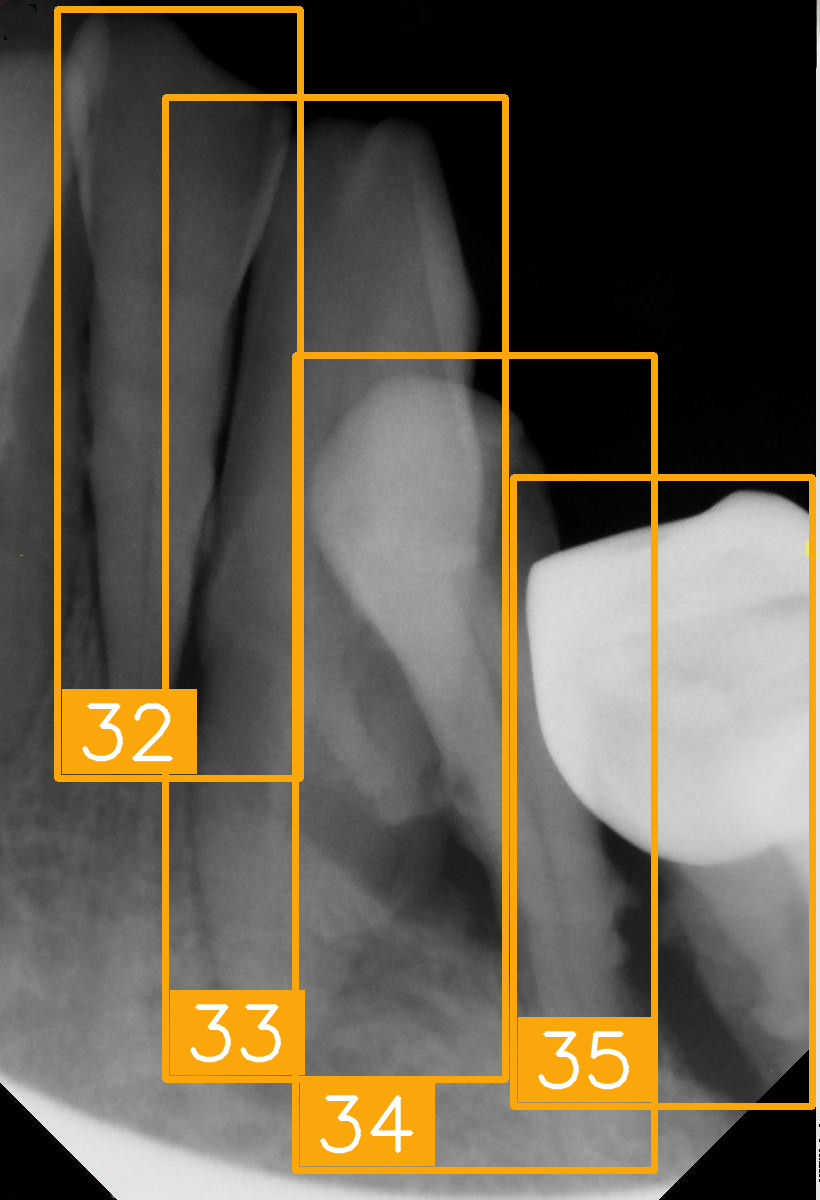

| Number | (e) | (f) | (g) | (h) |

| Condition | Fractured tooth; lower brightness | Overlapping | Implant | Implant |

| PA | ![]() | ![]() | ![]() | ![]() |

| FDI ground truth number | 45, 44, 43 | 32, 33, 34, 35 | 16, 15, 14, 13, 12 | 24, 25, 26 |

| Inference Time | 72.8 ms | 77.2 ms | 70.6 ms | 72.4 ms |